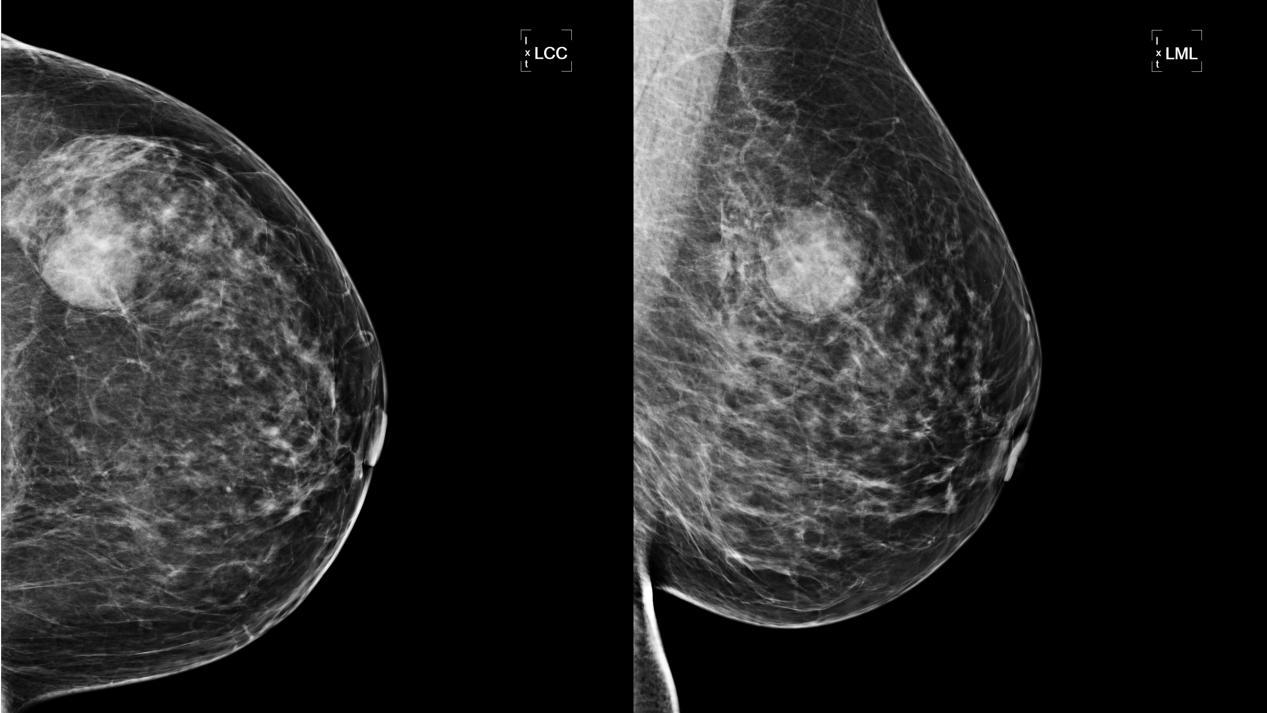

54岁的赵女士因乳腺疼痛不适,曾多次进行乳腺彩超检查,但未发现明显肿块,近日因胃部不适于来我院就诊,住院后进行胸部CT检查发现左乳占位,乳腺钼靶检查显示左乳外上象限肿块,外缘模糊且有分叶,BI-RADS分类4A。查体双乳未触及明显肿块,彩超也无法准确定位。结合患者病史、体检及相关辅助检查,与患者及家属充分沟通后,我院甲乳外科二病区医疗团队决定对其行钼靶定位引导下乳房肿块切除术。

术前,我院甲乳外科二病区林明副主任医师和北区放射科刘璇婷主治医师共同查阅了赵女士的钼靶影像资料,术中,根据钼靶定位结果,完整切除了肿块,手术获得成功,目前患者已经康复出院。此例钼靶引导下定位技术属皖东地区首例,填补了皖东地区该项技术空白。